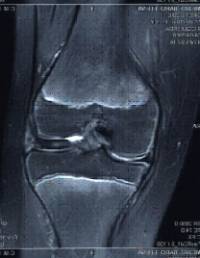

Osteocondritis disecante

Es una patología ocasionada por una isquemia transitoria del hueso subcondral pudiendo progresar hasta llegar a provocar el desprendimiento del mismo.

Se localiza con mayor frecuencia en el cóndilo femoral interno y su pronóstico varía en función de la edad de presentación (poco frecuente por debajo de los 10 años) y la estabilidad de la lesión.

El tratamiento pasa por limitar actividad deportiva de impacto , variar el eje de carga mecánico de la extremidad y puede ser necesaria la intervención quirúrgica.

Existen diferentes opciones de tratamiento quirúrgico en función de la estabilidad y localización del fragmento osteocondral (microperforaciones bajo control artroscópico , fijación in situ del fragmento osteocondral , empleo de injertos osteocondrales / mosaicoplastia ).

En los casos evolucionados con desprendimiento del fragmento osteocondral es preciso retirar el cuerpo libre articular ("ratón" articular) .